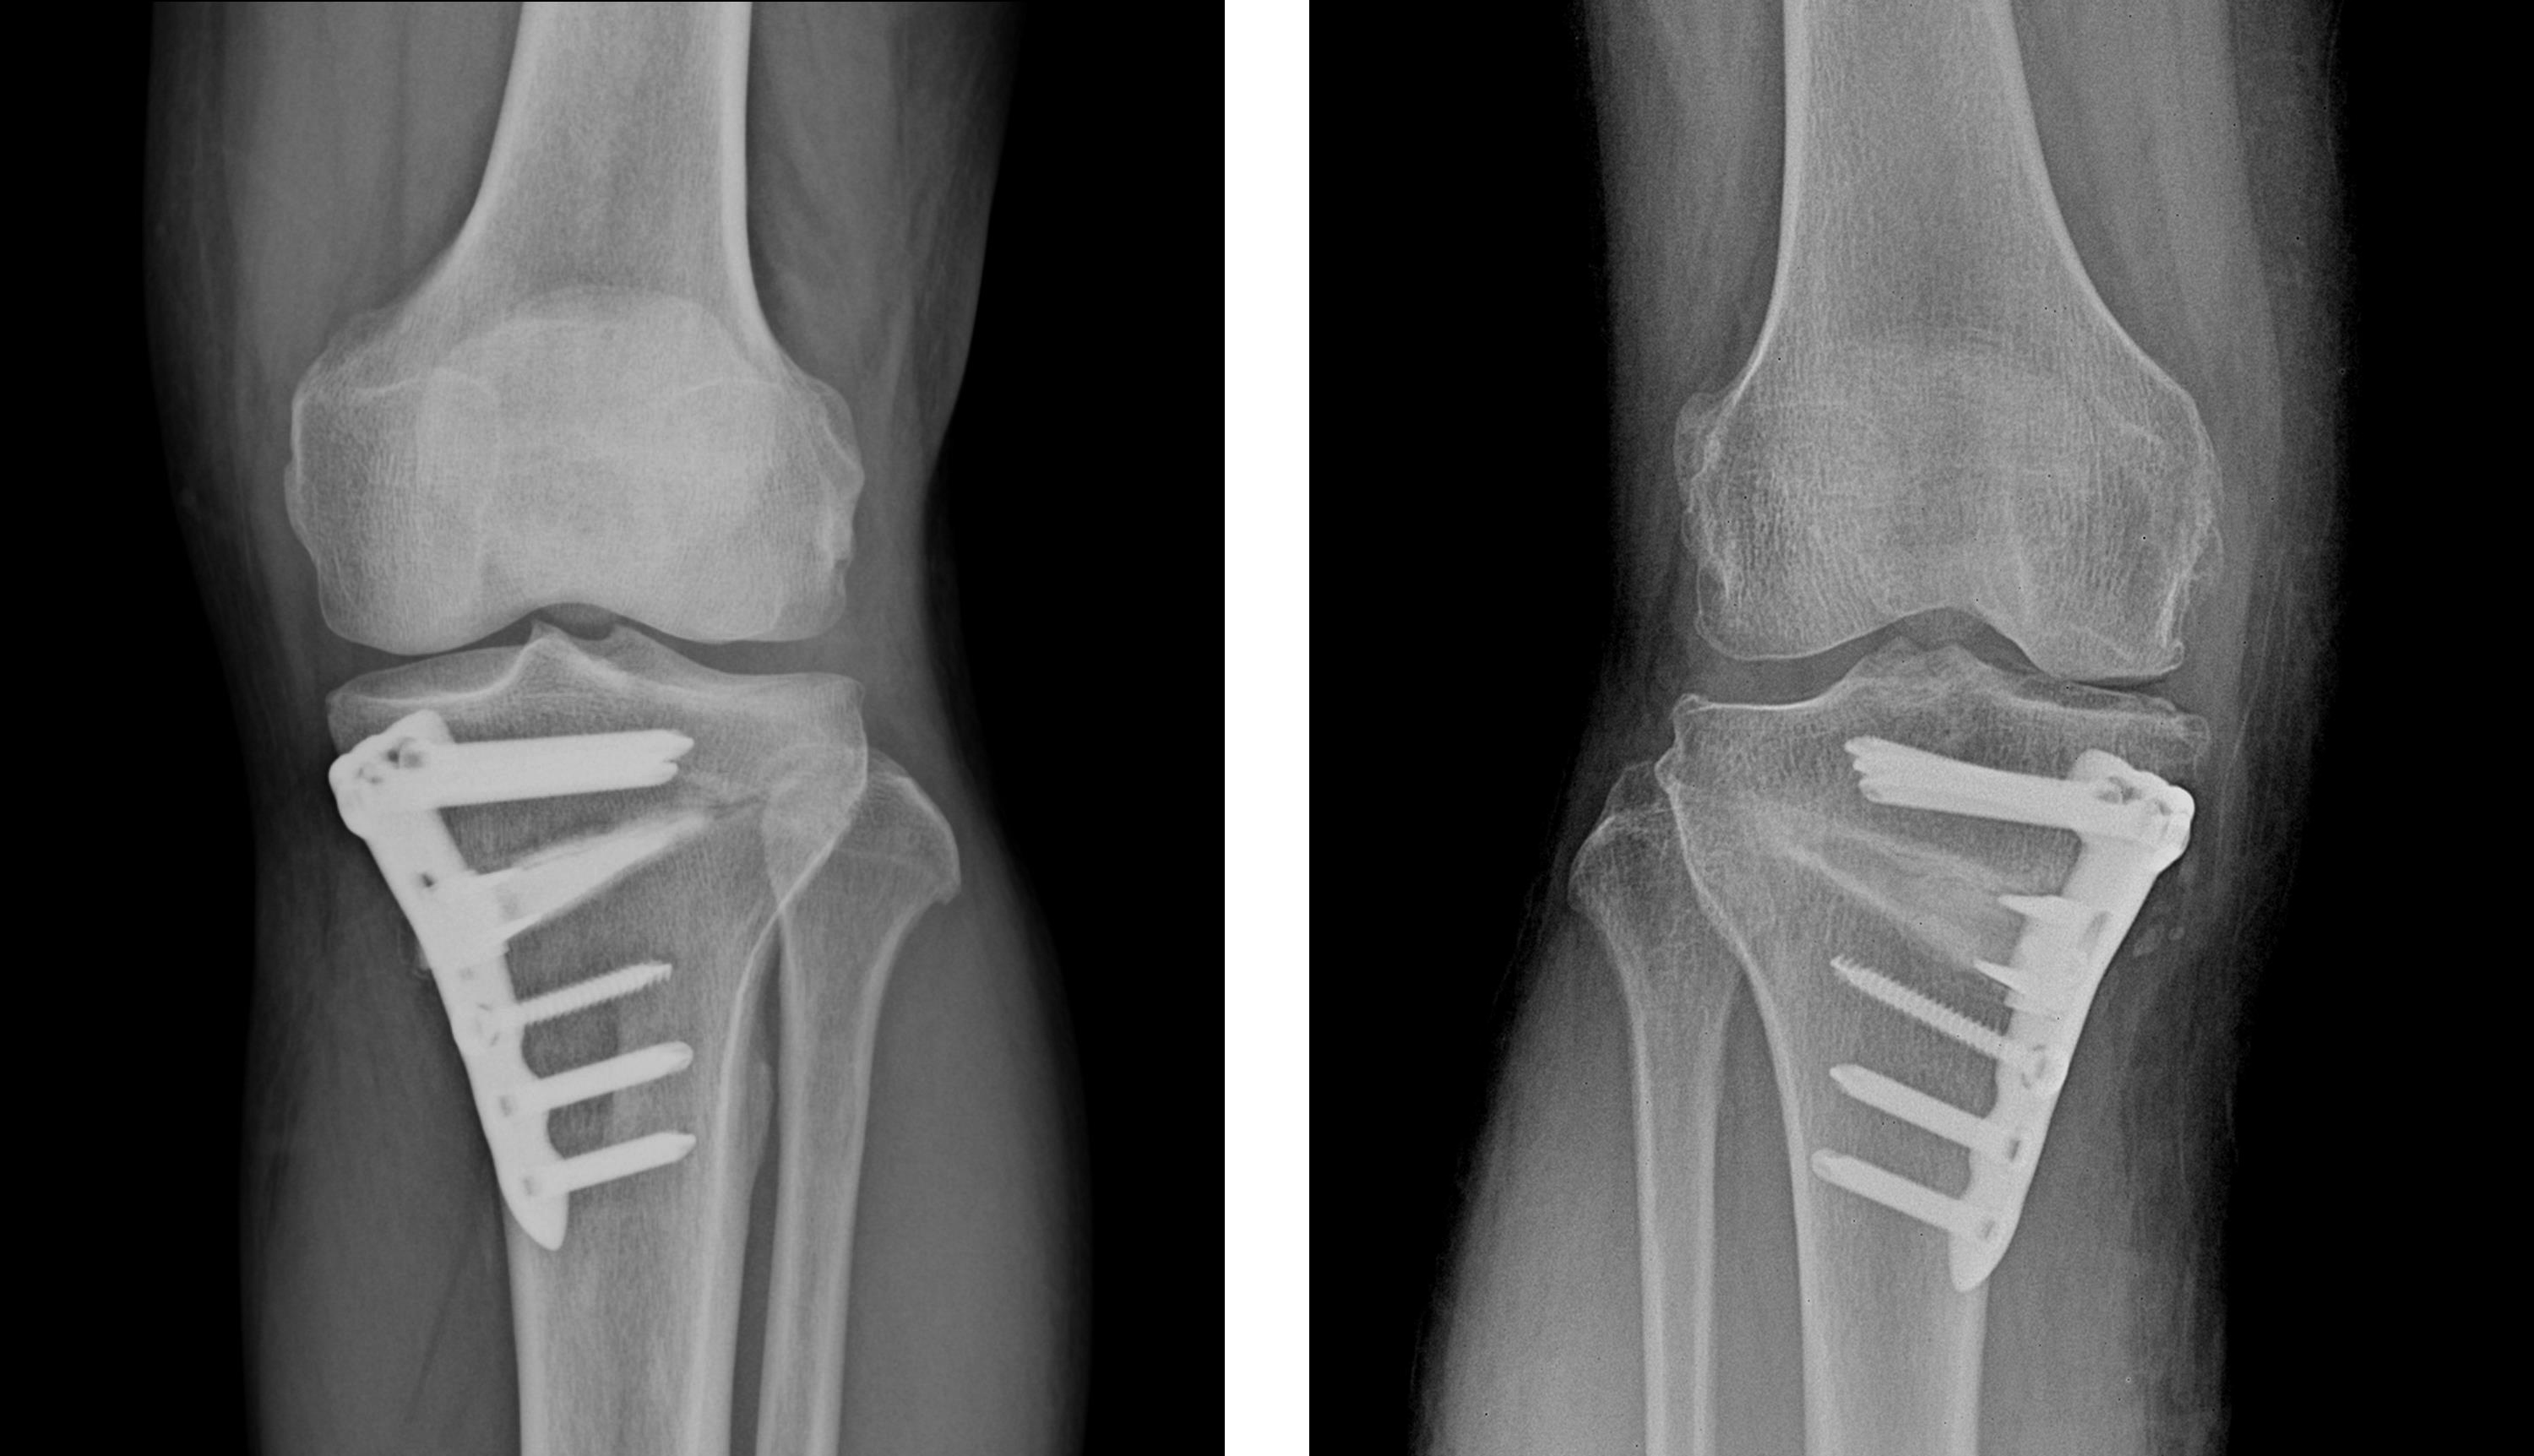

흰다리교정수술(절골술)